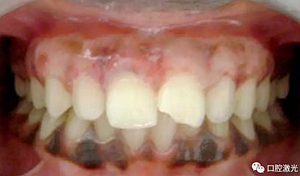

患者22歲,女性,主訴牙齦發(fā)黑??谇粰z查顯示牙齦部位呈黑色,但軟組織健康,沒有表皮粗糙或水腫現(xiàn)象。計(jì)劃使用半導(dǎo)體激光進(jìn)行治療。手術(shù)前患者無需表麻或局麻。采用光纖接觸方式,激光功率設(shè)定為1.5W至2W,連續(xù)模式。氣化黑色牙齦區(qū)域上皮組織。不斷重復(fù)該過程,直至足夠深度的牙齦軟組織表皮被去除干凈?;颊咝g(shù)后需采用漱口水進(jìn)行口腔護(hù)理。

術(shù)前